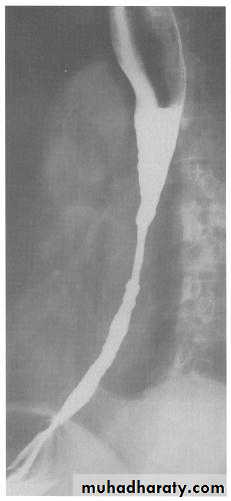

Narrowing :

1-the narrowing is Constant Short length (confined to cardia).

2-Regular and smooth.

3- No shouldering sign.

4-Tapering (Tip of pencil , cigar shape) Under left dome of diaphragm.

Achalasia continue

5. DILATATION (Sac like in proximal part )6-Undulating or spiky out line due to sluggish peristalsis.

7 Non- homogeneity of Barium due to food particles.

8-Air Barium level.

9- CXR shows widening of mediastinum.

10-Absence of fundal gas shadow.

7-Basal fibrosis in lungs due to repeated aspiration pneumonia .

LEFT: Dilated esophagus (arrows) appears as long, well-defined structure paralleling heart RIGHT: Dilated esophagus usually deviates to right. Narrowing (arrow) at hiatus.

LEFT: CT shows dilated esophagus (arrow) that led to esophagram.RIGHT: Esophagram shows narrowing (arrow) at level of hiatus.